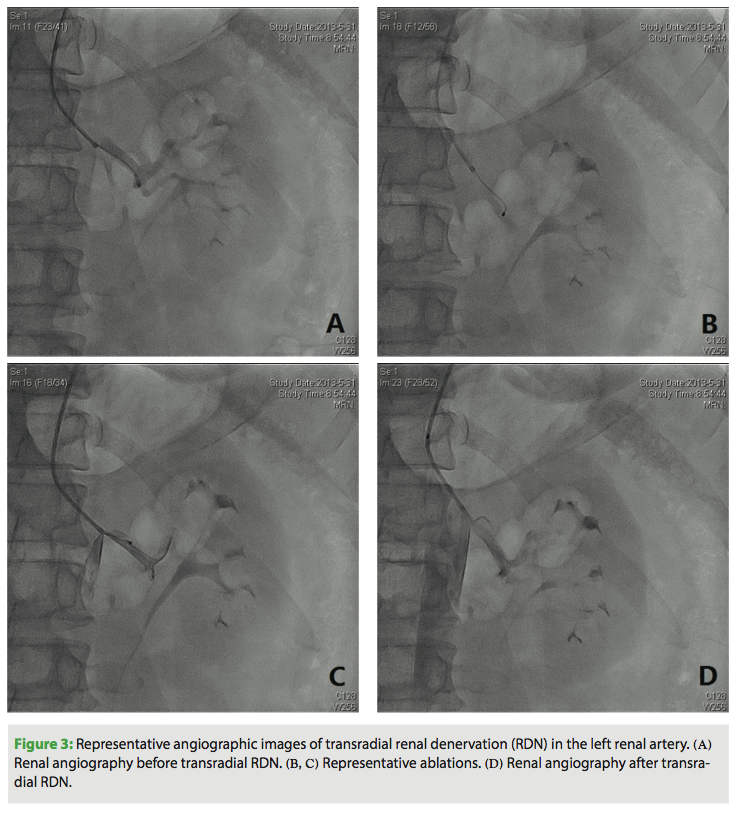

Under local anesthesia, using a modified Seldinger technique, a 6 Fr introducer sheath (Cordis Corporation) was inserted into the radial artery. A heparin bolus of 3000 units was administered intravenously and a continuous infusion of fentanyl and midazolam was started (5 µg and 0.2 mg/kg/h, respectively) and maintained until completion of RDN. In each case, the operator could easily advance a 6 Fr MPA1 guiding catheter (125 cm; Cordis Corporation) to the orifice of the renal arteries over a 0.035˝ HiWire angled hydrophilic guidewire (Cook Medical) (Figure 2). Renal angiography was first performed to further assess renal anatomy and dimensions (Figures 3A and 4A). Then, a 155 cm Iberis ablation catheter (AngioCare) was inserted and its tip was positioned proximal to the bifurcation of the renal artery. As previously described,3,4 4-8 ablations of 8 W or less and lasting up to 120 s each were performed along the length of the renal artery, separated both longitudinally and rotationally (Figures 3B, 3C, 4B, 4C). The procedure was repeated in the contralateral artery.

Supplementary doses of fentanyl or midazolam were given at the discretion of the anesthetist and guided by the clinical and hemodynamic responses. After the procedure, renal angiography was performed to evaluate changes in the renal arteries (Figures 3D, 4D). The access site sheath was removed immediately after the procedure, and a single tourniquet was pulled tight over the radial puncture site. Pressure was maintained on the puncture site for approximately 6 hours. Patients were typically discharged the day after the procedure.